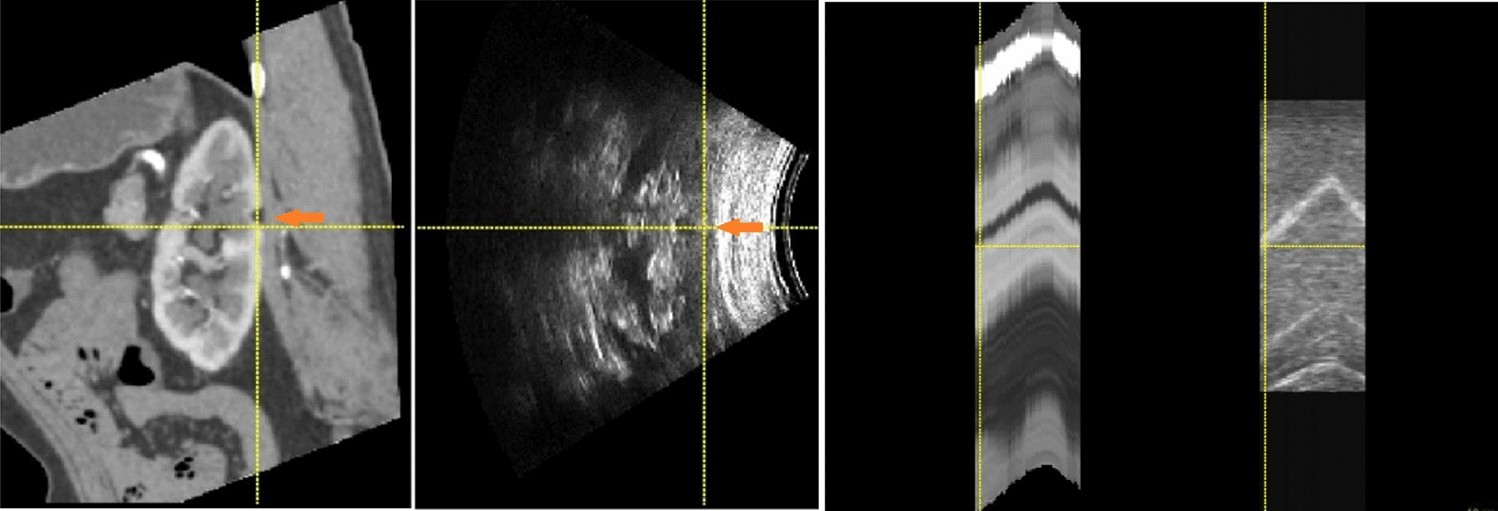

Figure 3

From: A two-step deep learning method for 3DCT-2DUS kidney registration during breathing

Example image pair to visualize target registration error (TRE) on (a) a small lesion in registered CT image and U/S image, (b) small lesion’s motion in respiration.